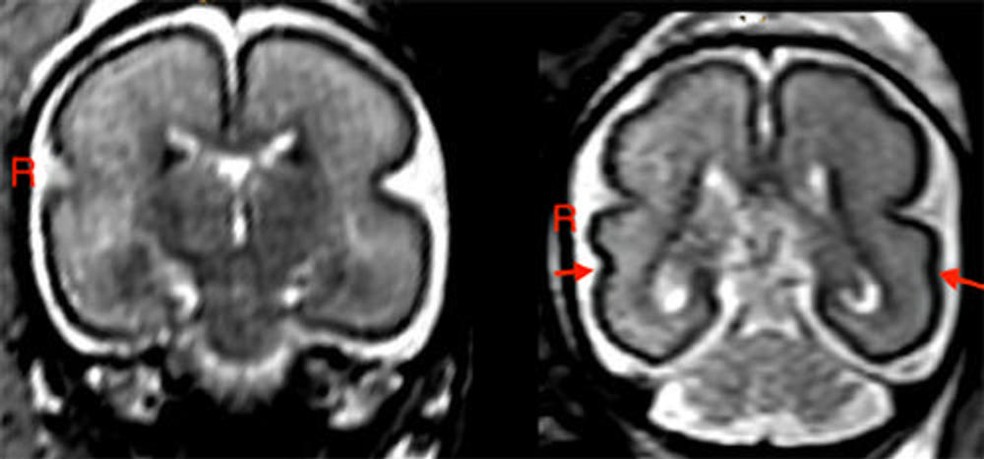

À esquerda, cérebro de feto exposto ao álcool entre 25 e 29 semanas de gestação: córtex liso nos lobos frontoparietal e temporal. À direita, cérebro de feto não exposto ao álcool: sulco temporal superior já está formado bilateralmente (setas vermelhas). — Foto: Divulgação/Universidade de Viena

Um estudo feito por pesquisadores da Universidade de Medicina de Viena revelou que uma taça de vinho por semana é capaz de provocar alterações físicas no cérebro do bebê. Exames de ressonância magnética apontou que crianças expostas a quantidades baixas de álcool no período pré-natal tinham um sulco temporal superior direito (STS) menos aprofundado — área cerebral envolvida na cognição e na linguagem.